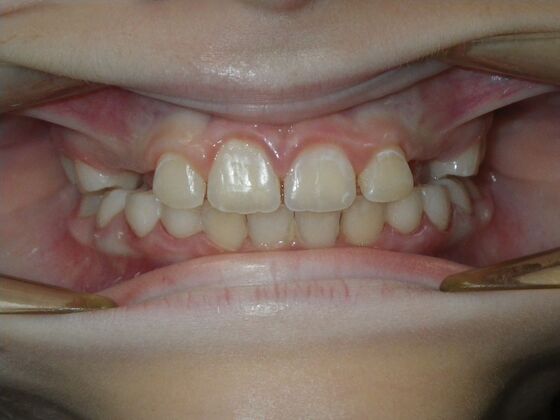

Patient presents with delayed eruption of the upper right central incisor and lower anterior crowding. Treatment plan to include exposure of right central incisor with bracket placement and correction of lower anterior crowding.